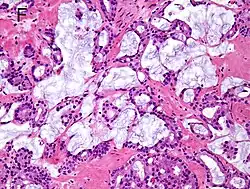

Microcystic carcinoma 11%[5]

• Cystic dilatation and rounded expansion of malignant glands[6]

• Lined by flat cells[6]

• Intraluminal crystalloids, and wispy blue intraluminal mucin[6]

• 34βE12- and p63-[6]

• AMACR+[6]

On (usually) adjacent acinar adeocarcinoma[6]